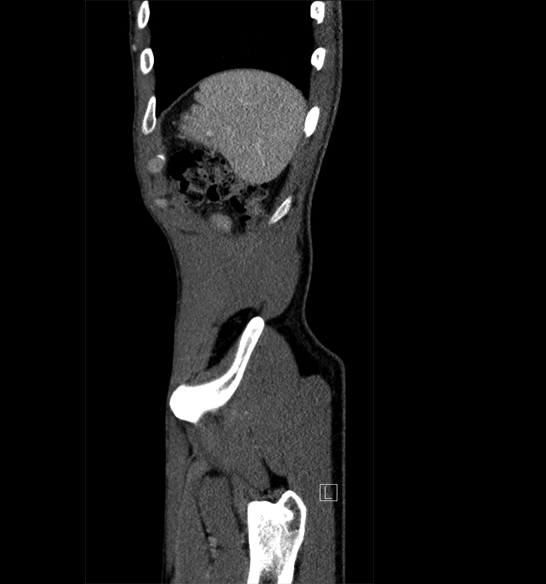

Body

Covers abdominal CT anatomy.